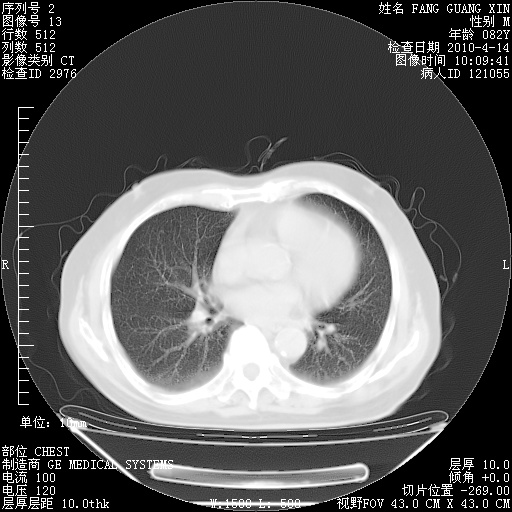

4月14日肺部CT